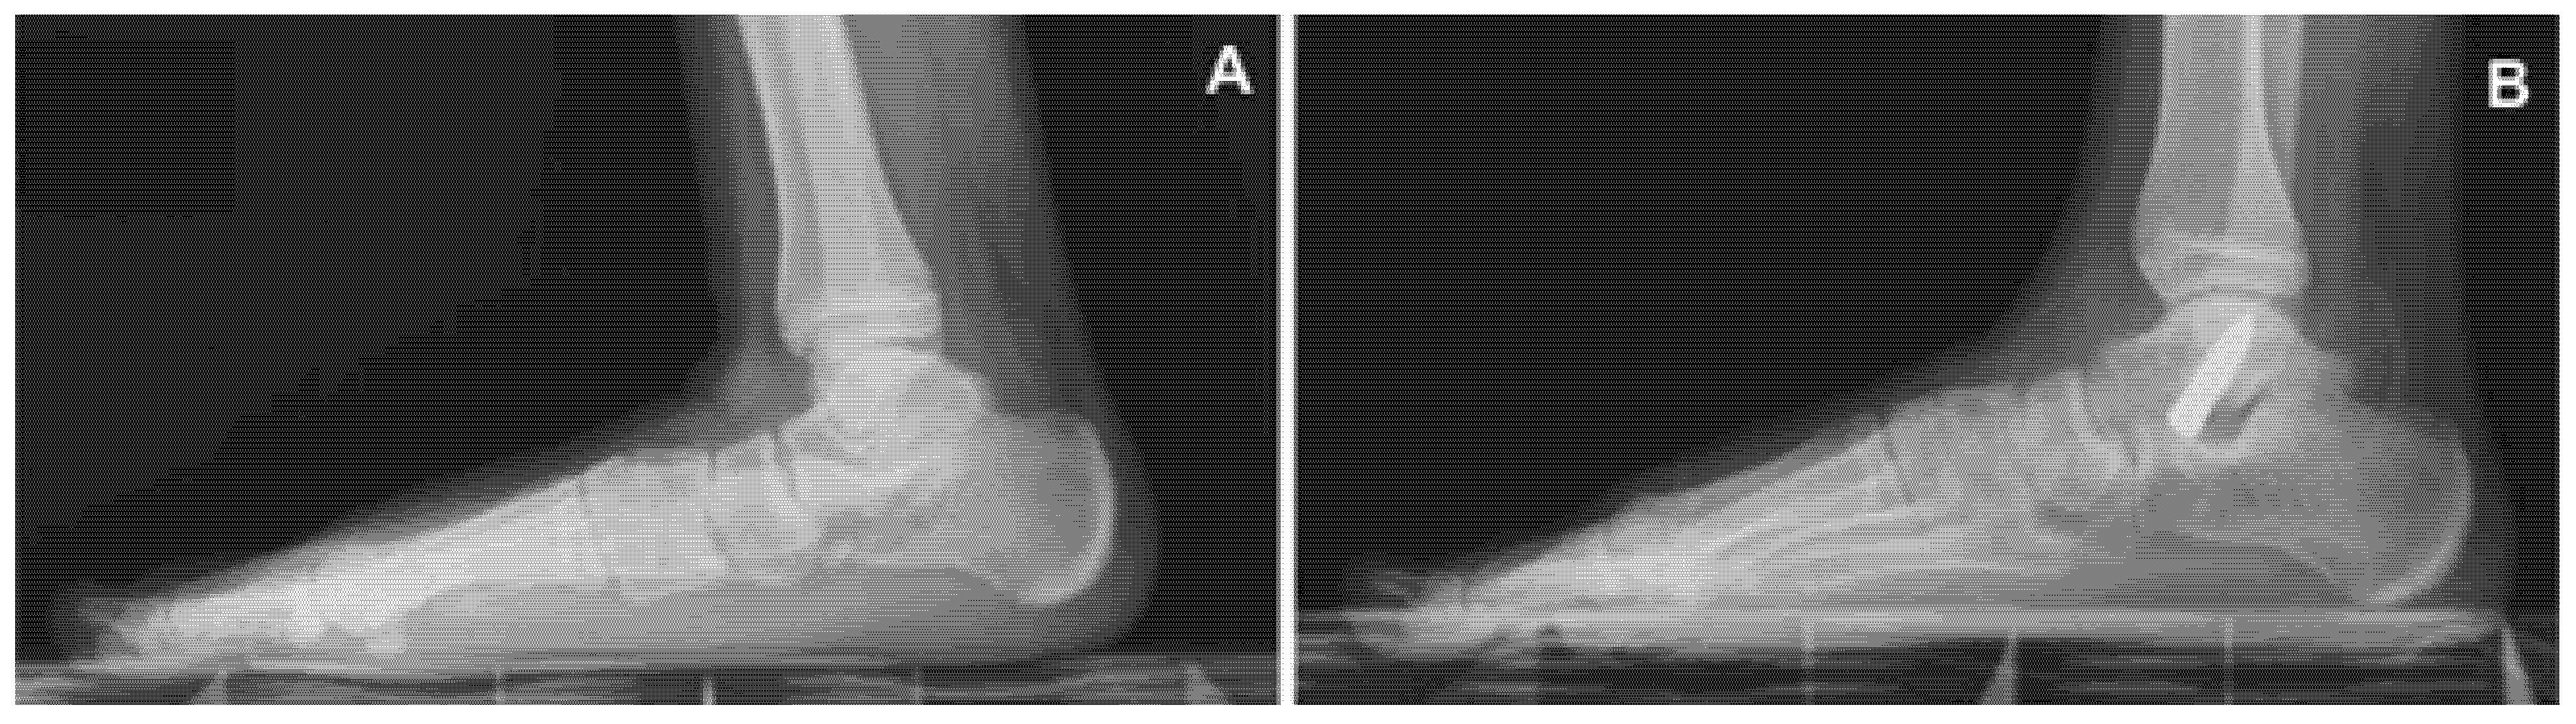

Figure 2 shows the results of gait registrations. The stride was significantly decreased in the patients before surgery, and only 24 months after the procedure it became similar to the control. The cadence was significantly decreased 24 months after surgery in comparison with the pre-surgical set. However, no differences were found between the control group and patients after the screw was removed. No significant differences were seen in the walking speed between patients at different endpoints and the controls. The cycle time increased significantly after the screw was removed when compared to the pre-op situation, and was similar to controls.

The analysis of gait before surgery confirmed that stride was significantly decreased in patients and increased gradually 12 months after surgery to regain normal values 24 months post-op. Similarly, the cycle time, significantly impaired in symptomatic flexible flatfoot, increased after surgery to reach a normal value. On the other hand, while the walking speed did not seem to be affected by the pathological condition, the cadence was significantly increased, and decreased after surgery till values were similar to controls. A patient with symptomatic flexible flatfoot walks with a shorter stride, increased cadence, slightly decreased speed, and decreased cycle time of the step. We previously demonstrated [12] that symptomatic flexible flatfoot is responsible for difficulties in walking and running, soreness and aching, as well as foot and ankle pain before surgical correction. Together with a subjective improvement of the overall situation after surgery, the gait analysis helped in demonstrating that the patients were objectively able to walk with a longer stride, decreased cadence, and longer cycle time. The walking speed seemed slower to catch up and this was probably related to the still decreased range of motion of the ankle joint.

Figure 2. Gait analysis data. Stride (A), cadence (B), walking speed (C), and cycle time (D) were considered in patients before surgery and 3, 12, and 24 months after surgery and compared with the control. (A): * indicates p < 0.05 for 24 months post-op vs. pre-op. (B): * indicates p < 0.05 for 3 and 24 months post-op vs. pre-op. (D): * indicates p < 0.05 for 24 months post-op vs. pre-op. m = months.